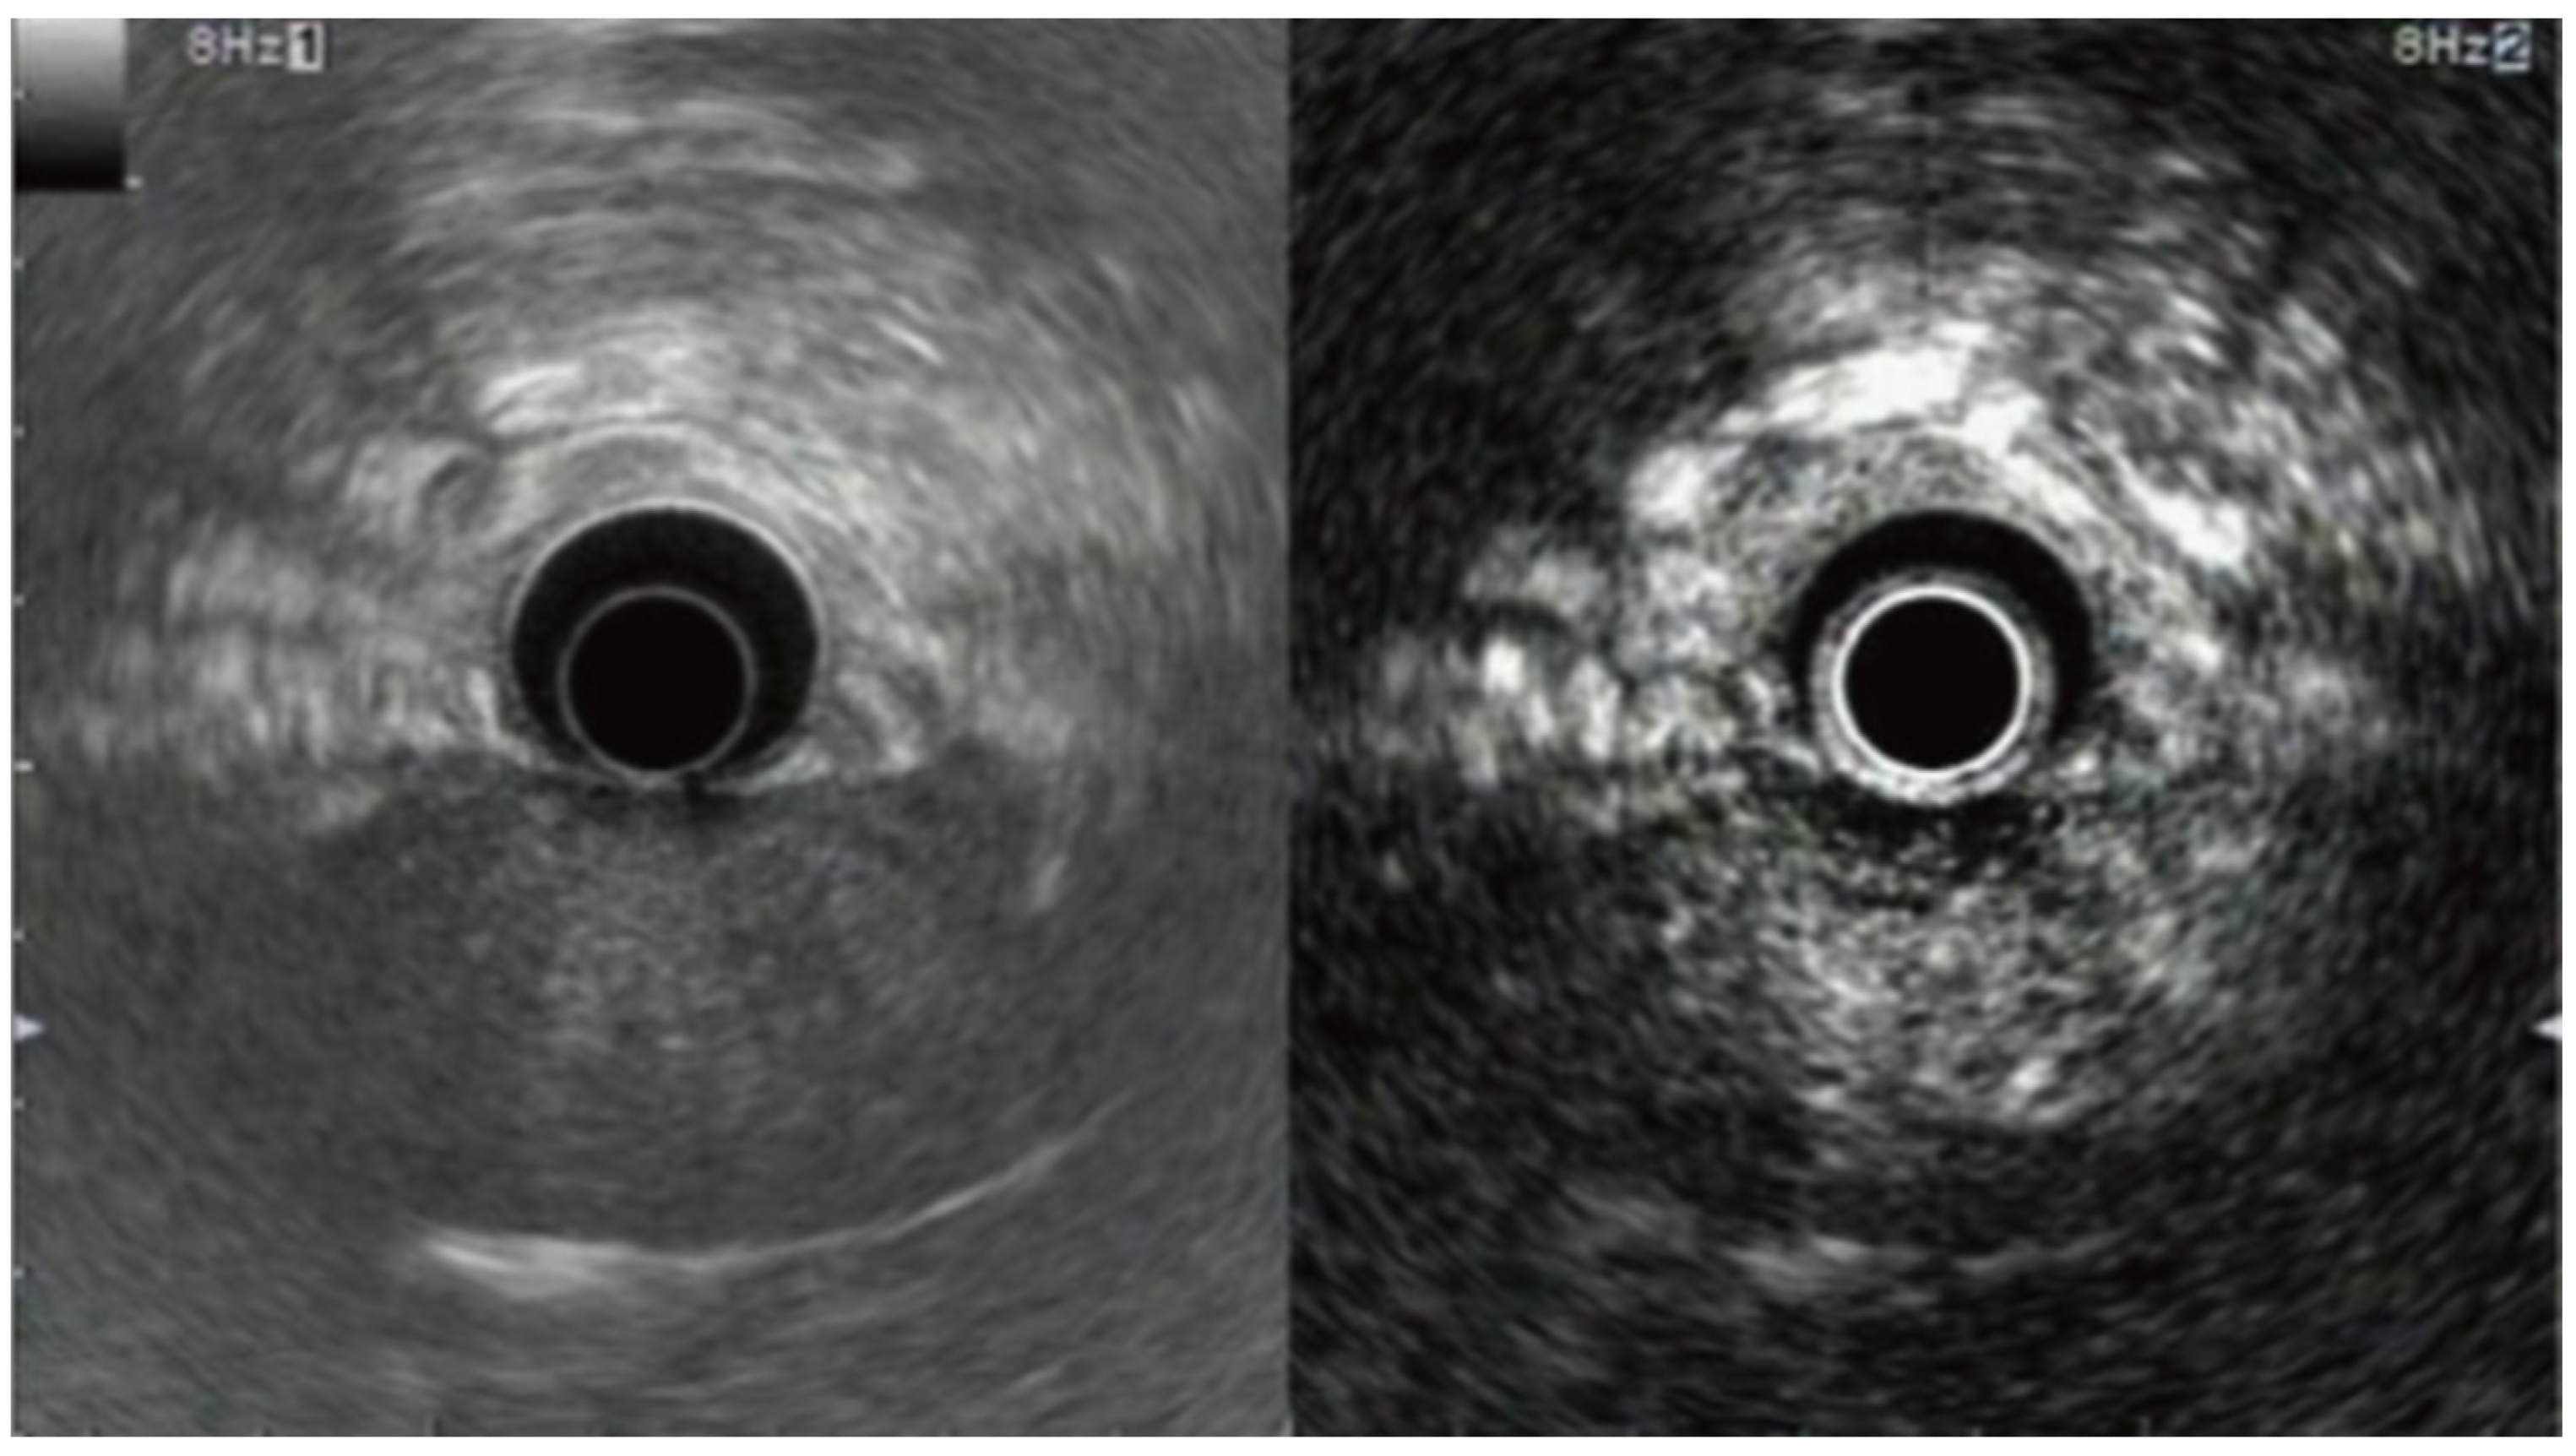

6. Contrast-Enhanced Endoscopic Ultrasound